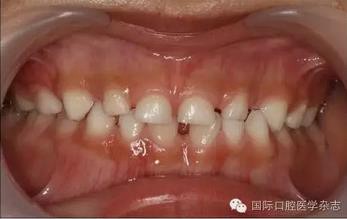

根尖X線片檢查偶然發(fā)現(xiàn):左側(cè)上頜乳尖牙呈雙根,髓腔寬大,牙根自接近根中1/3起至根尖分為明顯的近中及遠(yuǎn)中2個牙根(圖2)?;純杭议L知情同意后,拍攝其他3張乳尖牙根尖片,以觀察牙根是否有異常。X線片示:右側(cè)上頜乳尖牙呈雙根,且形態(tài)、大小及根分叉位置與左側(cè)相似(圖3)。雙側(cè)下頜乳尖牙的形態(tài)及牙根未見異常。詢問病史了解到,患兒體健,足月順產(chǎn),其母妊娠期間無感染或服藥史,患兒嬰幼兒期無外傷史,無兄弟姐妹。

圖3 右側(cè)上頜乳尖牙X線片

Fig 3 Maxillary right primary canine radiograph